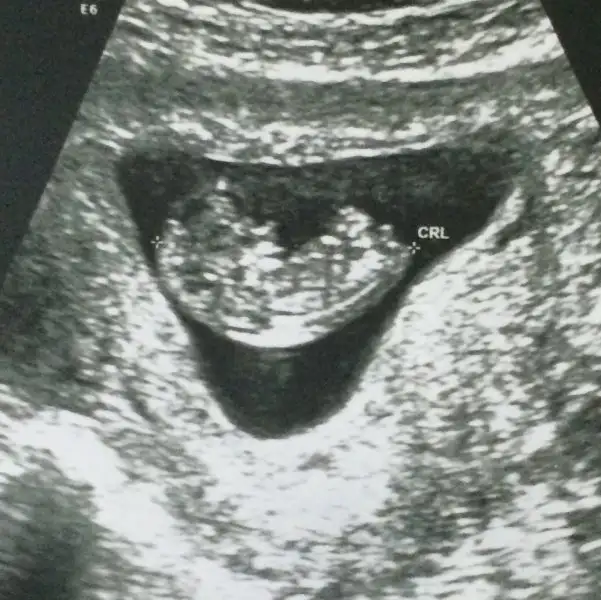

Merhaba burada 9+1 dik. Benim ultrason görüntümüde yorumlayabilirseniz sevinirim

Eklentiler

• 17671256_842657949208540_1834980796_n.webp

15,1 KB · Görüntüleme: 229